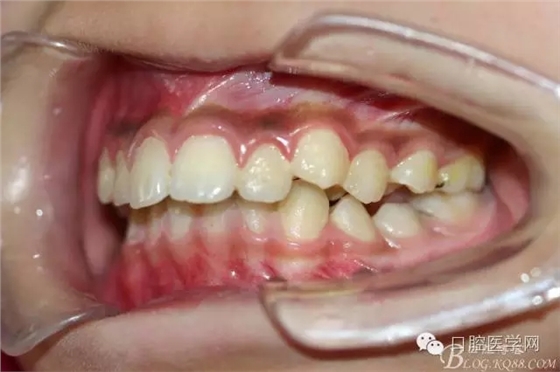

正畸后照片: